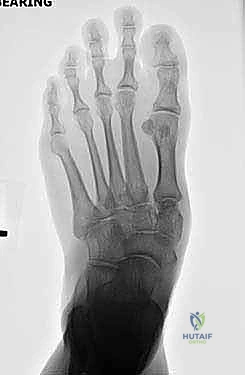

- الأشعة السينية أثناء الوقوف (Weight-bearing X-rays): وهي أهم أداة تشخيصية. الأشعة العادية والسرير فارغ لا تظهر المشكلة الحقيقية؛ يجب التقاط الأشعة والمريض يقف ليتحمل وزن الجسم، مما يظهر الانهيار الفعلي للمفاصل وتضيق المسافات بين العظام.

- الأشعة المقطعية (CT Scan): توفر صوراً ثلاثية الأبعاد للعظام، وهي ضرورية جداً للتخطيط الجراحي الدقيق وتحديد مدى التلف العظمي والزوايا المطلوبة للتثبيت.